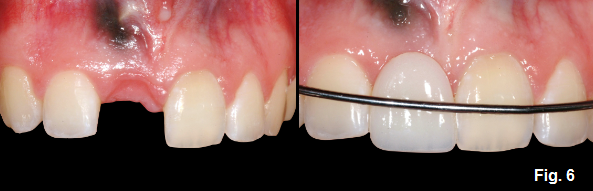

This will allow for the periosteum to grow over the remaining root creating a periosteal sling between the adjacent teeth over the edentulous ridge and underlying root. The creation of the periosteal sling will allow some vertical ridge development in the edentulous site due to the tension created by the eruption of the adjacent teeth, while the remaining root continues to undergo replacement resorption. (Fig. 5)

The difficulty in managing these patients with extraction of the ankylosed tooth is providing interim tooth replacement until the cessation of growth (this is especially true in males where growth may not be completed until 21-22 years of age). As can be seen though, when the patient is ready to undergo implant treatment, the ridge height is relatively good, making the management of the ridge more predictable for an implant or a pontic. (Fig. 6)